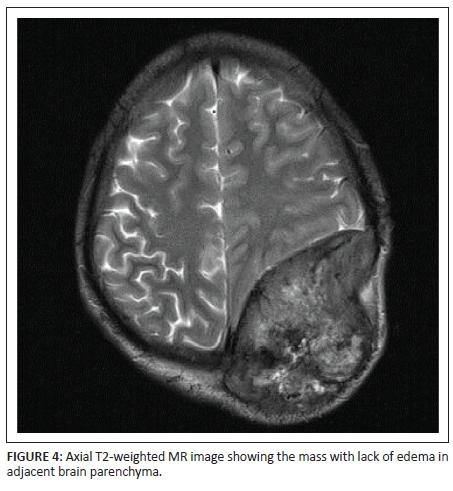

X-rays of the skull showed a well-defined lytic lesion in the left parietal bone with an associated large soft tissue component. No marginal sclerosis or periosteal reaction was noted (Figure 1a and 1b). Non-contrast computed tomography (NCCT) revealed a well-defined heterogeneous hyperdense mass lesion centred on the left parietal bone causing bone destruction, compressing the adjacent brain parenchyma and bulging into the scalp. A few small bony fragments were seen at the periphery of the lesion (Figure 2). Magnetic resonance imaging (MRI) of the brain with contrast demonstrated a well-defined heterogeneously enhancing soft tissue mass lesion measuring 8.0 cm × 7.9 cm × 6.8 cm causing destruction of the left parietal bone and bulging into the scalp. Some flow voids were seen with the mass. No restricted diffusion or surrounding oedema was noted. There was mass effect with compression of adjacent brain parenchyma and mild midline shift to the right side. The mass was compressing adjacent superior sagittal sinus but not invading it (Figures 3, 4, 5 and 6). Skeletal survey of the body revealed no other lytic lesions anywhere in the body.

On radiography, SPB presents as a well-defined osteolytic lesion with clear margins and narrow zone of transition. There is no bony sclerosis or periosteal reaction. The lesion is hyperdense on NCCT and shows marked homogenous enhancement with contrast. Small bony fragments may be seen at the periphery. On MRI, SPB appears isointense on T1-weighted images and hyperintense on T2-weighted images. Intratumoural flow voids have been described. The lesion shows dense but heterogeneous enhancement with contrast.3,5,6